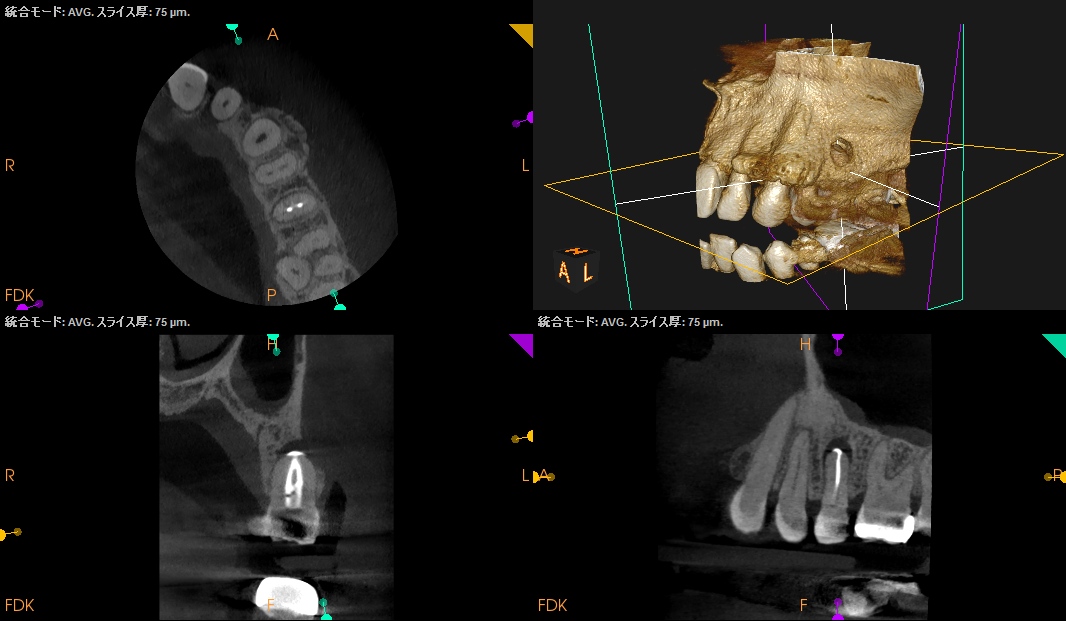

#13 RCT 1yr recall(2026.2.26)

1年前と比較した。

根尖病変は大きく縮小し、臨床症状(圧痛)も消失したのでかかりつけ医の先生には最終補綴を依頼した。

次回はさらに1年後である。